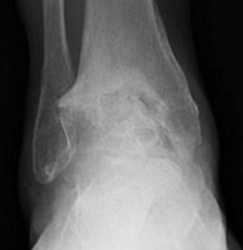

Классификация артроза голеностопного сустава.

Полная облитерация сустава

Для диагностие выполняются рентгенограммы в прямой, боковой и косых проекциях, с нагрузкой весом тела. На рентгенограммах определяется сужение суставного пространства, субхондральный склероз, формирование кист, деформация, рост остеофитов.